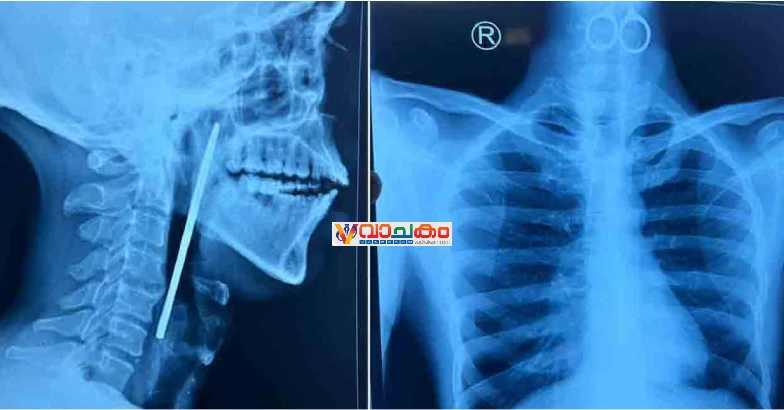

കോഴിക്കോട് : മാനസികാരോഗ്യ കേന്ദ്രത്തിലെ രോഗി വിഴുങ്ങിയത് കത്രിക. പിന്നാലെ കോഴിക്കോട് ഗവ. മെഡിക്കൽ കോളജ് ആശുപത്രിയിൽ നടത്തിയ ശസ്ത്രക്രിയയിലൂടെ പുറത്തെടുത്തു.

തിങ്കളാഴ്ച രാത്രി നടത്തിയ അടിയന്തിര ശസ്ത്രക്രിയയിലൂടെയാണ് 15 സെന്റിമീറ്ററോളം നീളമുള്ള കത്രിക പുറത്തെടുത്തത്.

ഭക്ഷണം കഴിക്കാത്തതിനെ തുടർന്ന് തിങ്കളാഴ്ച വൈകിട്ടാണ് യുവാവിനെ അത്യാഹിത വിഭാഗത്തിൽ പ്രവേശിപ്പിച്ചത്. അന്നനാളത്തിൽ കത്രിക കുടുങ്ങി കിടക്കുന്നതായി എക്സറേ പരിശോധനയിൽ കണ്ടെത്തിയത്.